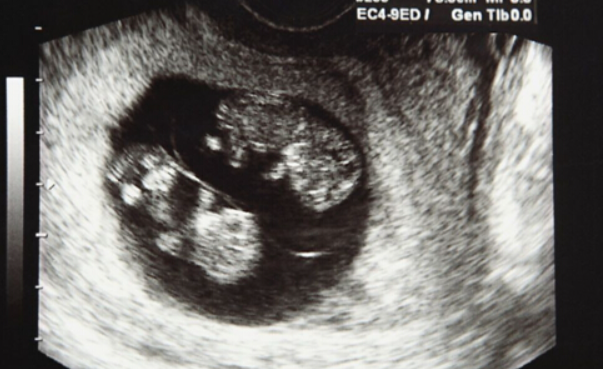

格鲁吉亚试管婴儿双胎概率有多高?”最近这个疑问的提问率有点高,这个问题也让我想起去年李女士去格鲁吉亚试管婴儿的经历。当时李女士因为卵巢功能衰退,在国内某医院尝试了两次都失败了,最后抱着试试看的心态去了格鲁吉亚SMC皇家医疗生殖中心(SILK Medical Clinic,SMC医院)。结果不仅成功怀孕,还收获了一对龙凤胎!

二、李女士的“双胎奇迹”是怎么实现的?

2、移植前需要慎重评估:虽然移植多胎可以提高怀双胎概率,但多胎妊娠可能导致早产、妊娠高血压等问题,并不是想移植双胞胎就能移植双胞胎的。格鲁吉亚SMC医院的医生会根据子宫环境评估风险,确保两个婴儿在健康发育的情况下也能确保母体的健康。